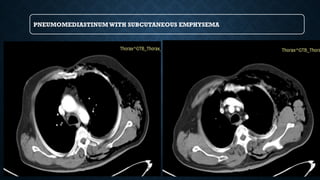

PNEUMOMEDIASTINUM: CT

PNEUMOMEDIASTINUMWITH SUBCUTANEOUS EMPHYSEMA

PNEUMOMEDIASTINUM

• Usually from ruptured alveoli

• Can also be from trachea, bronchi,

esophagus, bowel and neck injuries

SIGNS

• Linear paratracheal lucencies

• Air along heart border

• “V” sign at aortic-diaphragm

junction

• Continuous diaphragm sign